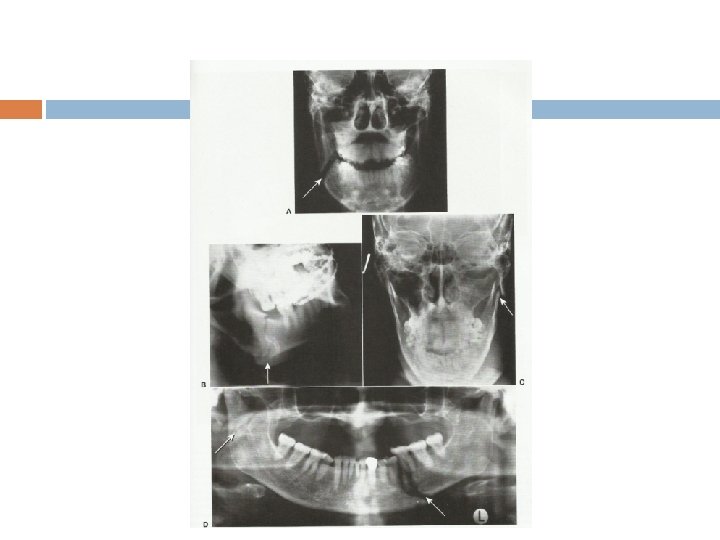

Anatomic distribution of mandibular fracture

Maxillary fractures, comminuted mandibular ramus/body fractures and bilateral condyle fractures.

Le Fort midfacial fractures